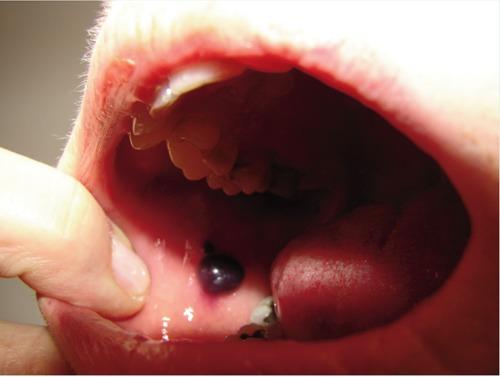

Angina bullosa hemorrhagica is a rare and benign disorder, usually localized in the subepithelial layer of the oral, pharyngeal and esophageal mucosa. The lesions are characterized by their sudden onset. They appear as a painless, tense, dark red and blood-filled blister in the mouth that rapidly expand and rupture spontaneously in 24-48 hours. The underlying etiopathology remains ill defined, although it may be a multifactorial phenomenon including diabetes, and steroid inhalers. The condition is not attributable to blood dyscrasias, nor other vesicular-bullous disorders. In this study, eleven patients with such blisters are described. Physical examination of the patients revealed a single blister with hemorrhagic content localized in the oral mucosa. Biopsy of the lesions showed sub epithelial blisters with a mild infiltrate. In general practice, dermatologists could face a blood-filled bullous lesion of the oral mucosa. Recognition is, therefore, of great importance for dermatologists.

出血性大疱性心绞痛是一种罕见的良性疾病,通常局限于口腔、咽部和食管黏膜的上皮下层。病变的特点是突然发作。它们表现为口腔内无痛、紧张、暗红色且充满血液的水疱,在24 - 48小时内迅速扩大并自发破裂。尽管其潜在病因可能是包括糖尿病和类固醇吸入器在内的多因素现象,但其确切病因仍不明确。该病症与血液系统疾病或其他水疱大疱性疾病无关。在本研究中,描述了11例有此类水疱的患者。对患者的体格检查发现口腔黏膜有一个充满血性内容物的单个水疱。病变活检显示上皮下疱伴轻度浸润。在一般临床实践中,皮肤科医生可能会遇到口腔黏膜充满血液的大疱性病变。因此,识别对于皮肤科医生非常重要。